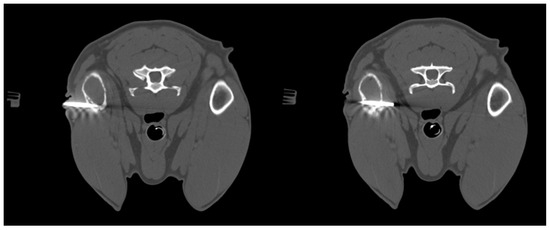

Postoperative Computed Tomographic Assessment of the Complete Resection of an Infiltrative Lipoma Compressing the Spinal Cord in a Dog

by Junyoung Kim, Kitae Kim, Dayoung Oh, Hyunwook Myung, Jihye Choi and Junghee Yoon

Infiltrative lipomas, which are locally invasive tumors composed of well-differentiated adipocytes, are histologically identical to lipomas but have a tendency to infiltrate adjacent muscle and fibrous tissue without metastasis, such as muscle; connective tissue; bone; and, in rare cases, peripheral nerves and the [...] Read more.

Infiltrative lipomas, which are locally invasive tumors composed of well-differentiated adipocytes, are histologically identical to lipomas but have a tendency to infiltrate adjacent muscle and fibrous tissue without metastasis, such as muscle; connective tissue; bone; and, in rare cases, peripheral nerves and the spinal cord. They differ from liposarcomas yet also exhibit neoplastic cell infiltration and often recur despite surgical removal. A 10-year-old spayed Maltese female dog presented with hindlimb paresis and back pain for two months. Computed tomography and magnetic resonance imaging revealed an extensive fatty mass impinging on the vertebral canal, compressing the spinal cord, and extending into the surrounding muscle layers and thoracic cavity. The mass was surgically removed, and subsequent postoperative computed tomography confirmed complete removal of the mass using Vitrea® advanced visualization fat measurement. Histopathological analysis confirmed that the mass was an infiltrative lipoma. The patient’s symptoms completely resolved after surgery, with no recurrence reported at the 2-year follow-up. This case highlights the benefits of using postoperative computed tomography combined with the automated fat measurement technique to determine whether reoperation is necessary or to predict patient prognosis by identifying potential residual lipoma post-surgery. Full article